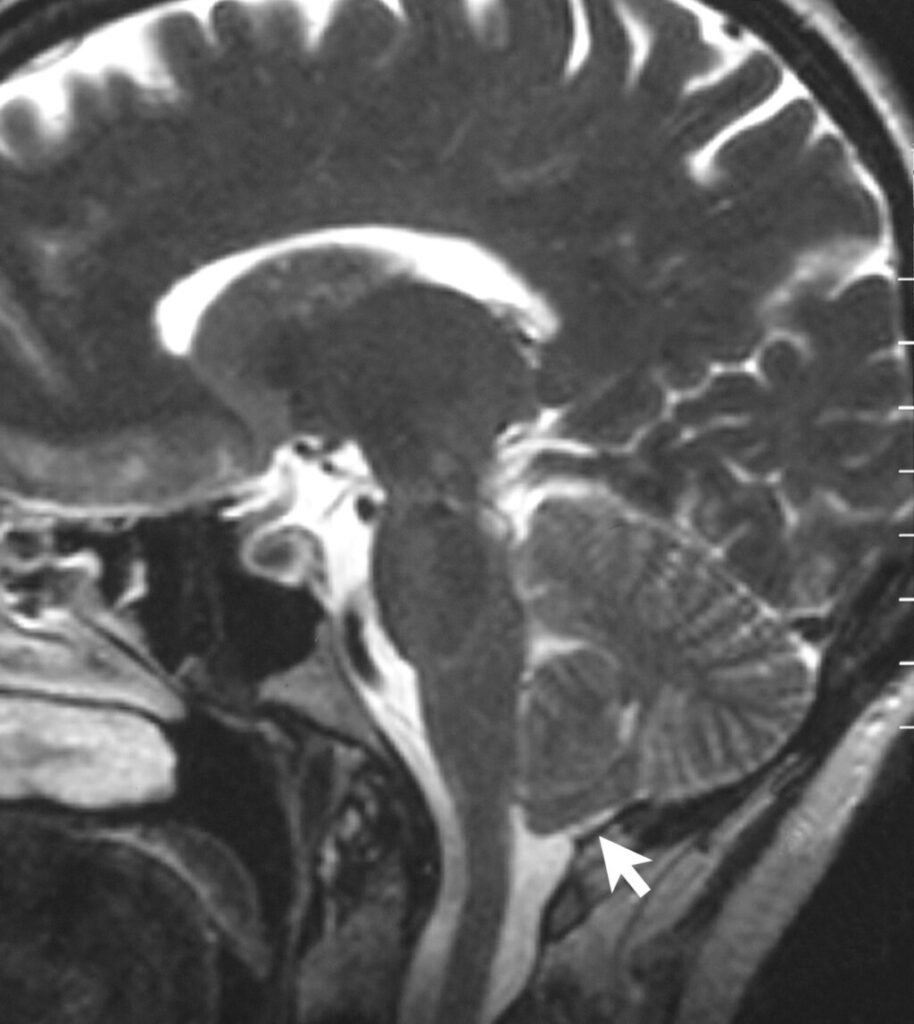

Chiari malformation type 1 affects about 1 in 100 people and can cause symptoms such as headaches, dizziness, and balance issues. Using 3D models from CT scans of 46 affected individuals and 57 controls, researchers found that Chiari skulls had a compressed cerebellum and a flatter cranial base, traits that closely resemble those of Homo neanderthalensis. In contrast, the control group’s skull aligned more closely with modern Homo sapiens.